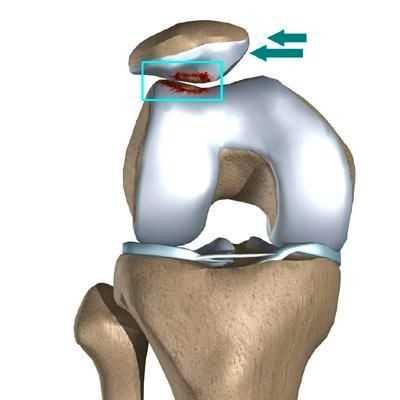

Иногда повреждения переднелатеральных структур коленного сустава сопровождаются отрывным переломом кортикальной пластинки от переднелатеральной поверхности проксимального метаэпифиза большеберцовой кости, который впервые был описан P. Segond в 1879 г. и, таким образом, визуализируется на рентгенограммах [12].

Латеральный вывих надколенника характеризуется разрывом медиального ретинакулюма (медиальной пателло-феморальной связки) коленного сустава. Повторный вывих у пациента — главный признак не выполнения медиальной пателло-феморальной связкой своих функций из-за перерастяжения после первичной травмы.

Часто предпосылкой к формированию латеральной нестабильности надколенника становится дисплазия феморопателлярного отдела — врожденного состояния, характеризующегося нарушениями соотношений между надколенником и недостаточно выраженной межмыщелковой бороздой бедренной кости (см. рис.).

Наличие дисплазии различной степени выраженности ведет к тому, что движения надколенника при сгибании и разгибании в коленном суставе происходят с тенденцией к его латеральному смещению. При дополнительном травматическом воздействии это приводит к возникновению полноценного вывиха.